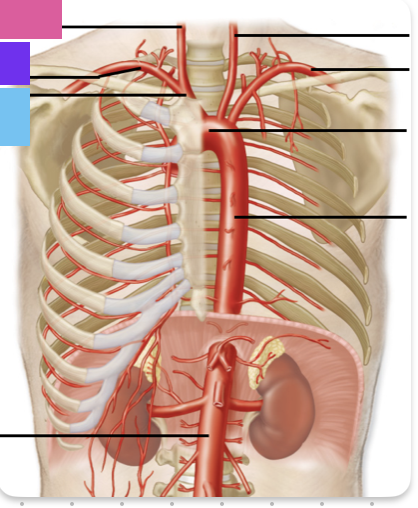

ascending aorta

aortic arch

brachiocephalic trunk (blue)

right common carotid artery

right subclavian artery

left common carotid artery (grey)

left subclavian artery (black)

descending aorta

thoracic aorta

abdominal aorta